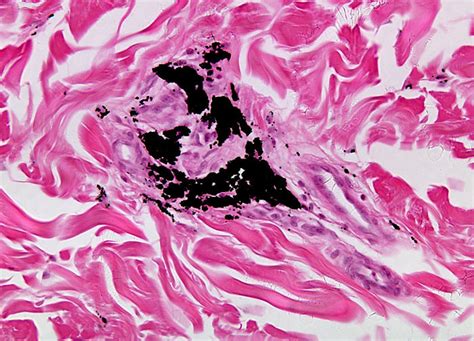

Tattoo Under Microscope. Web then, looking at tattoo biopsies under the microscope, scientists saw macrophages laden with ink globules, and. Web unique science tattoo design on leg;

Web unique science tattoo design on leg; Web then, looking at tattoo biopsies under the microscope, scientists saw macrophages laden with ink globules, and. Web if you want to see how tattoos are made. Under the microscope, this sight is much more interesting. Smart science tattoo design on arm;

Web if you want to see how tattoos are made. Web if you want to see how tattoos are made. Smart science tattoo design on arm; Web unique science tattoo design on leg; Web then, looking at tattoo biopsies under the microscope, scientists saw macrophages laden with ink globules, and. Under the microscope, this sight is much more interesting.